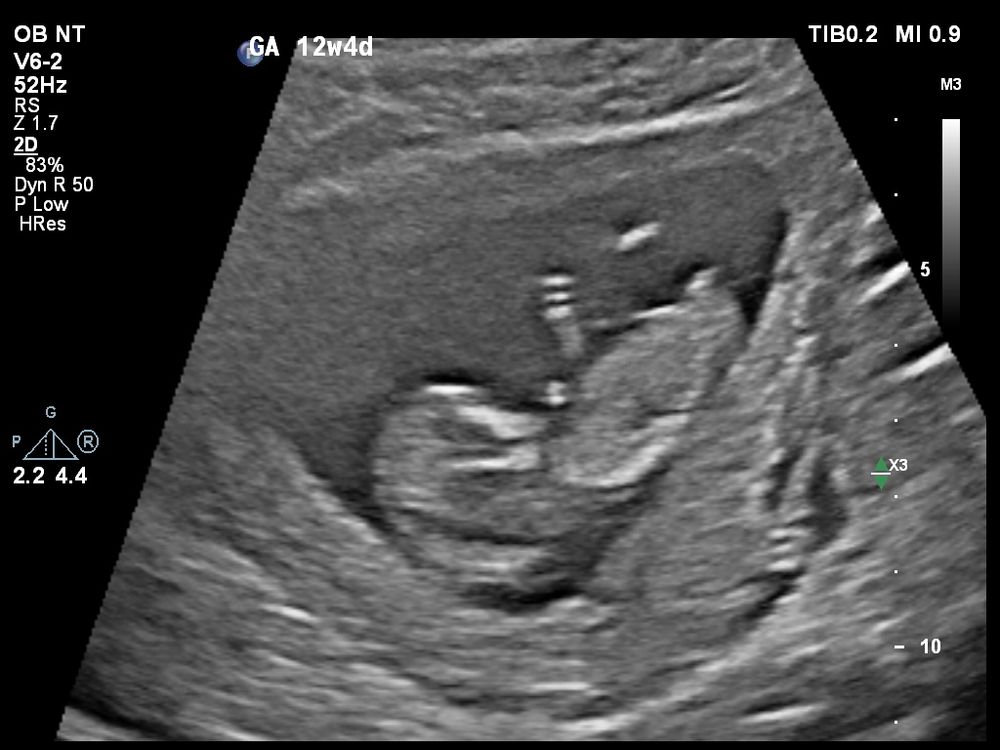

Первый скрининг, половой бугорок? 😁

Сегодня был первый скрининг, всё хорошо у малыша/малышки, но у меня теперь маленький нерв весь день заставляет разбирать этот половой бугорок. Во время УЗИ я будто увидела бугорок параллельный, на девчонку, а смотрю на фотографии - вижу под углом, на мальчишку 😁